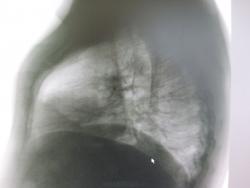

Шаровидное образование в левом лёгком

Мужчина молодого возраста проходил профосмотр и выявилось шаровидная тень. Жалоб пациент не предъявляет. От томограмм врачи отказались, сказав, что повезут его сразу на КТ. Как будут развиваться события дальше я не знаю. Хотелось бы посоветоваться с коллегами, что это. Предварительно я написал о кальцинате, добр. опухоль.

Слева в верхней доле, без томограмм тяжело что то говорить.

Томографируйте , если сомневаетесь.

Так на КТ уже направили.